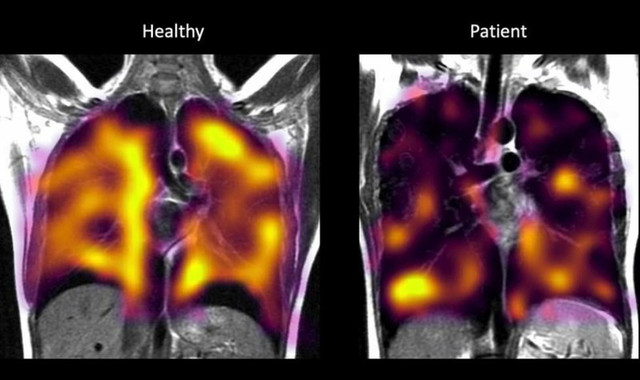

Lượng khí vào phổi của người khỏe mạnh (trái) nhiều hơn so với lượng khí vào phổi của người mắc di chứng hậu COVID-19. Ảnh: ĐẠI HỌC OXFORD

Các nhà nghiên cứu đã phát hiện ở hầu hết những người bị di chứng hậu Covid-19, lượng khí được truyền ít hơn so với các đối chứng khỏe mạnh. Nhóm bệnh nhân từng nhập viện để điều trị COVID-19 cũng có những bất thường tương tự.